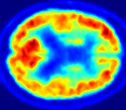

| MRI | PET | U-PET | U-PET (no att.) | pix2pix |

4.0.2 Qualitative Results

Looking at sample synthetic PET images in Fig. 3, it can be seen that all of the models are able to make reasonable predictions. The outputs of the U-PET and U-PET (no att.) look very similar and are smoothed compared to the input. The pix2pix predicts more details, which seem to be important for the discriminator. However, even though this model has finer predictions, the intensity values are worse compared to the U-PET and U-PET (no att.) as seen in Fig. 2; an example is given in Fig. 3 in the second row.

From a clinical perspective, the synthetic generated PET show a smoother version of the real PET images but keep the same pattern of FDG uptake, especially, hypometabolism in the respective brain areas. This backs up our hypothesis, that MRI contains information that correlates with the functional information of PET images. Moreover, the synthetic PET could be used as complementary visualization for physicians beyond the task of classification.